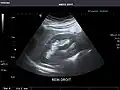

Right kidney -

Kidneys: Right and left kidneys measure 11.5 cm and 12 cm in length respectively. No hydronephrosis. Small left lower pole kidney cyst.